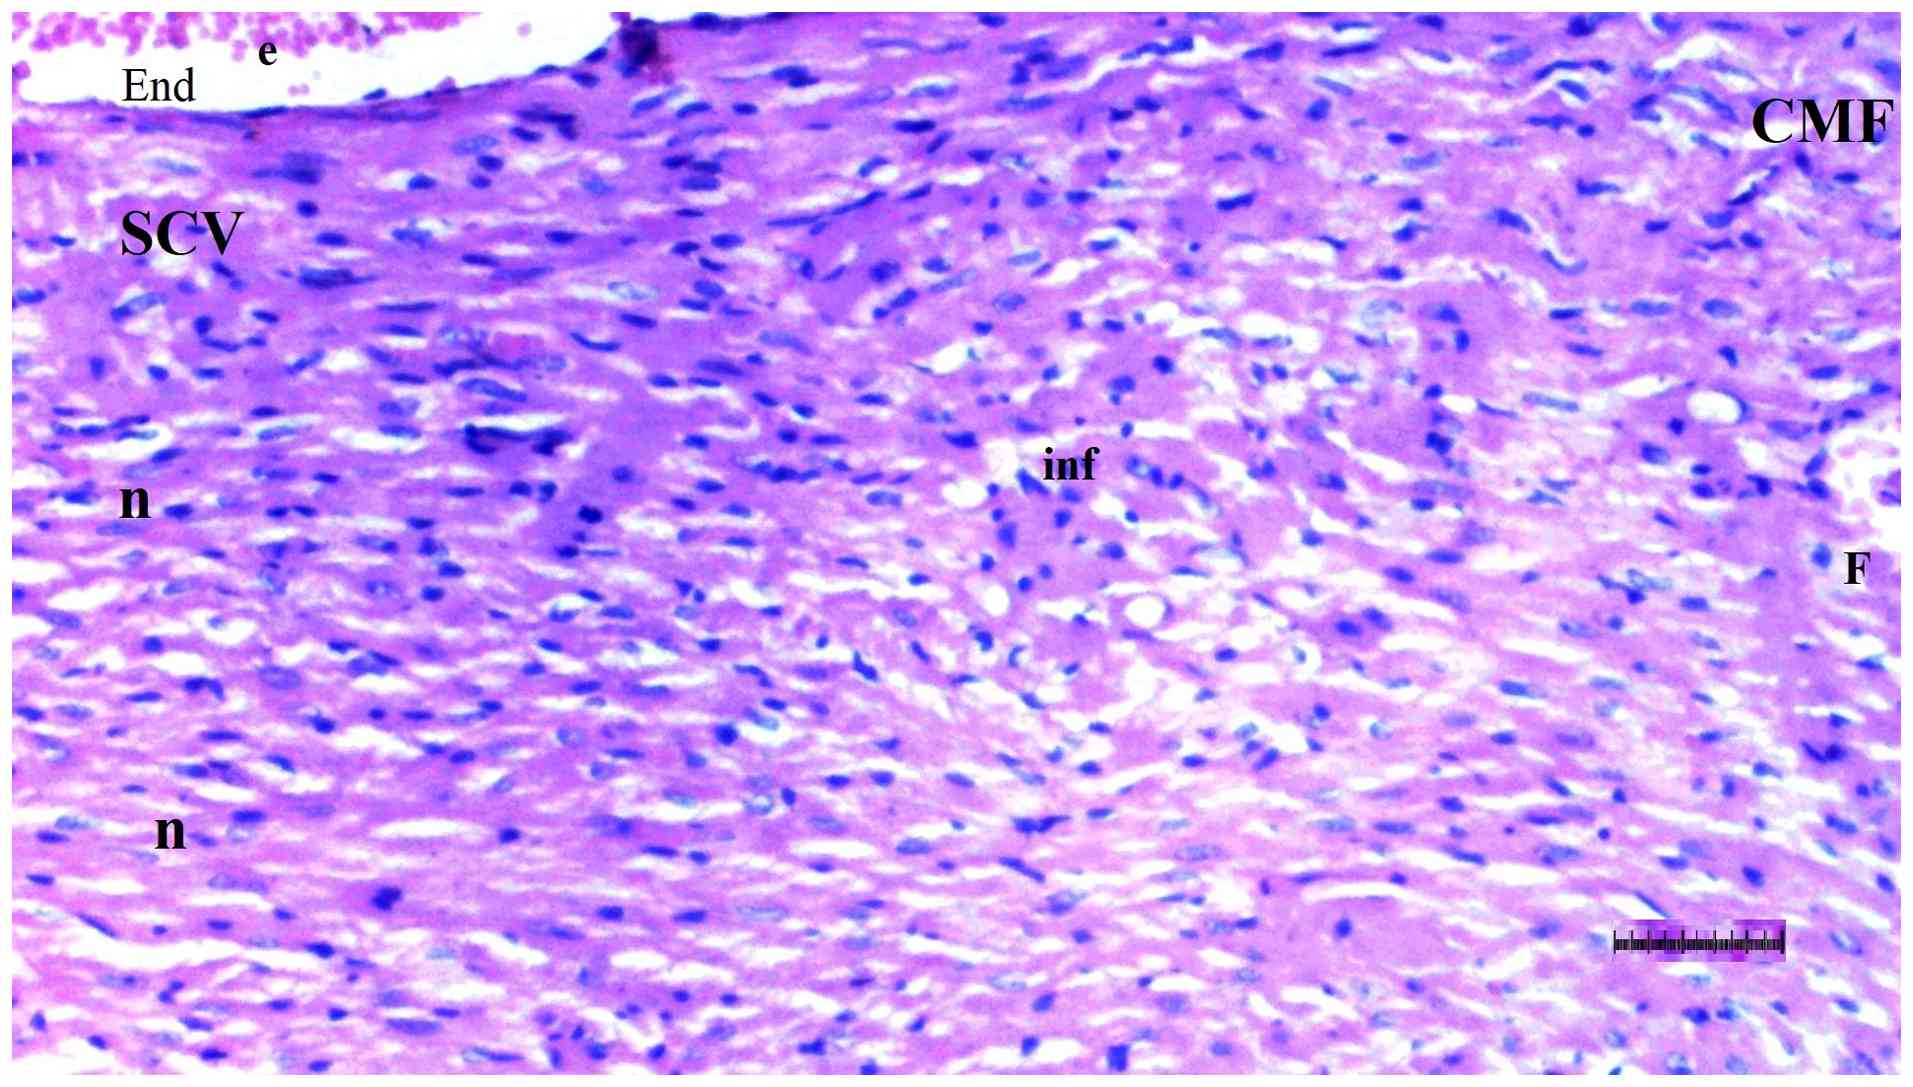

Representative light microscopy of

heart tissue from the diabetic control group. H&E staining.

Magnification, x100. CMF, cardiac muscle fibers; F, fibrosis; inf,

inflammation.

Figure 6

Representative light microscopy of heart tissue from the diabetic control group. H&E staining. Magnification, x100. CMF, cardiac muscle fibers; F, fibrosis; inf, inflammation.

Histopathological examination of heart tissue

Inflammation varied significantly among groups (P=0.036). The DM/SEP group exhibited a significantly higher degree of inflammation compared with the S group (P=0.013) (Table II; Fig. 5, Fig. 6, Fig. 7 and Fig. 8). Interstitial fibrosis differed significantly among groups (P=0.040); it was significantly greater in the DM/SEP group compared with the S and D groups (P=0.004 and P=0.012, respectively); however, it was significantly reduced in the FUL/C-60 group compared with the DM/SEP group (P=0.040) (Table II; Fig. 5, Fig. 6, Fig. 7 and Fig. 8).